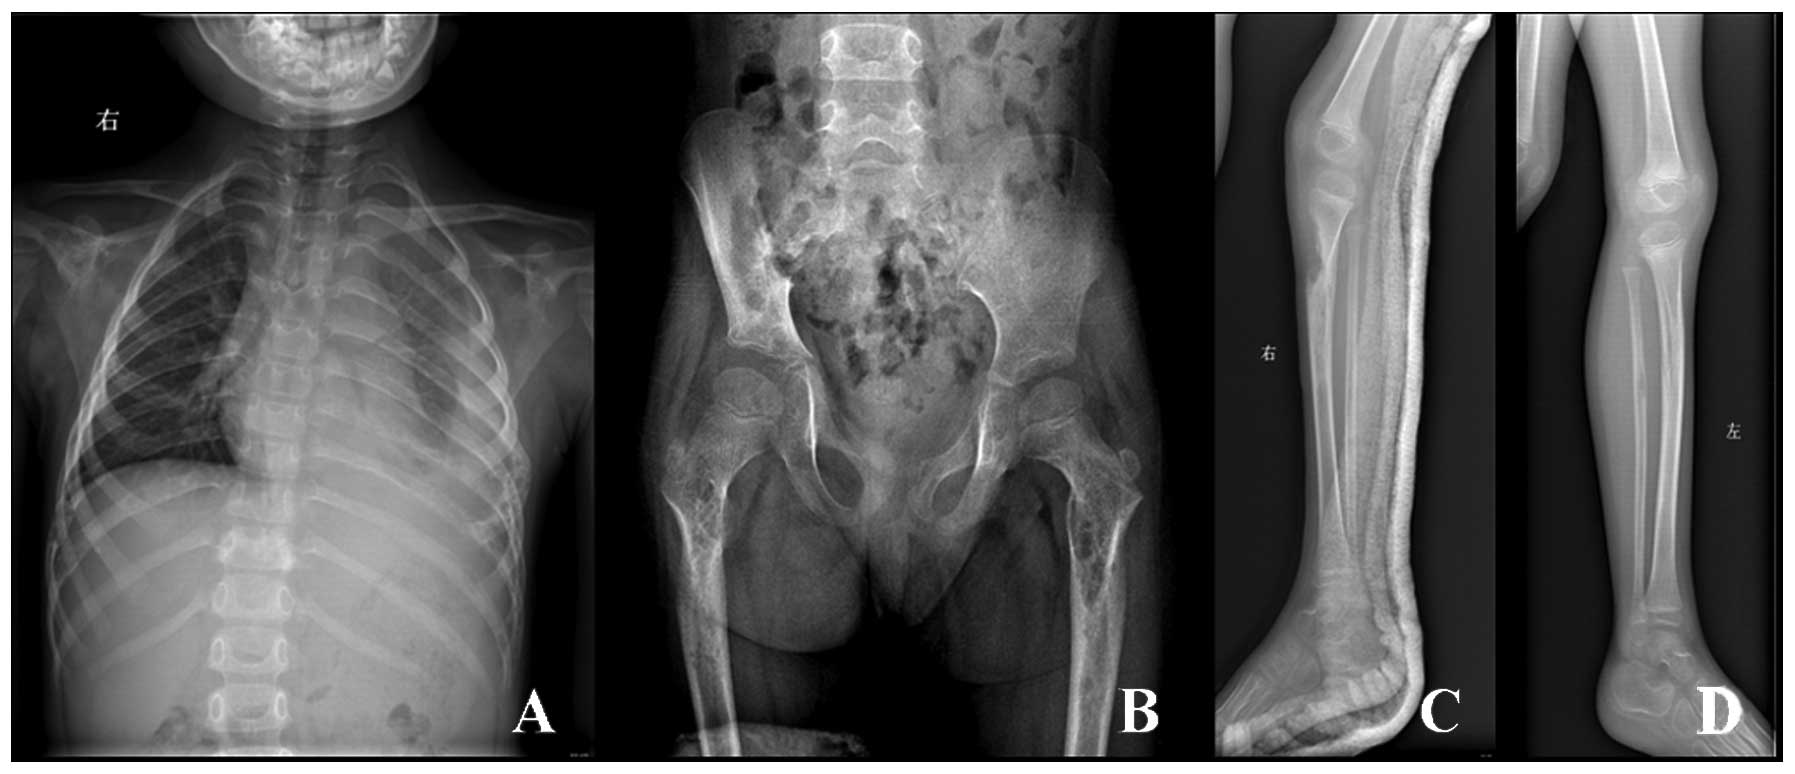

Визуальные материалы, связанные с болезнью Горхема-Стаута